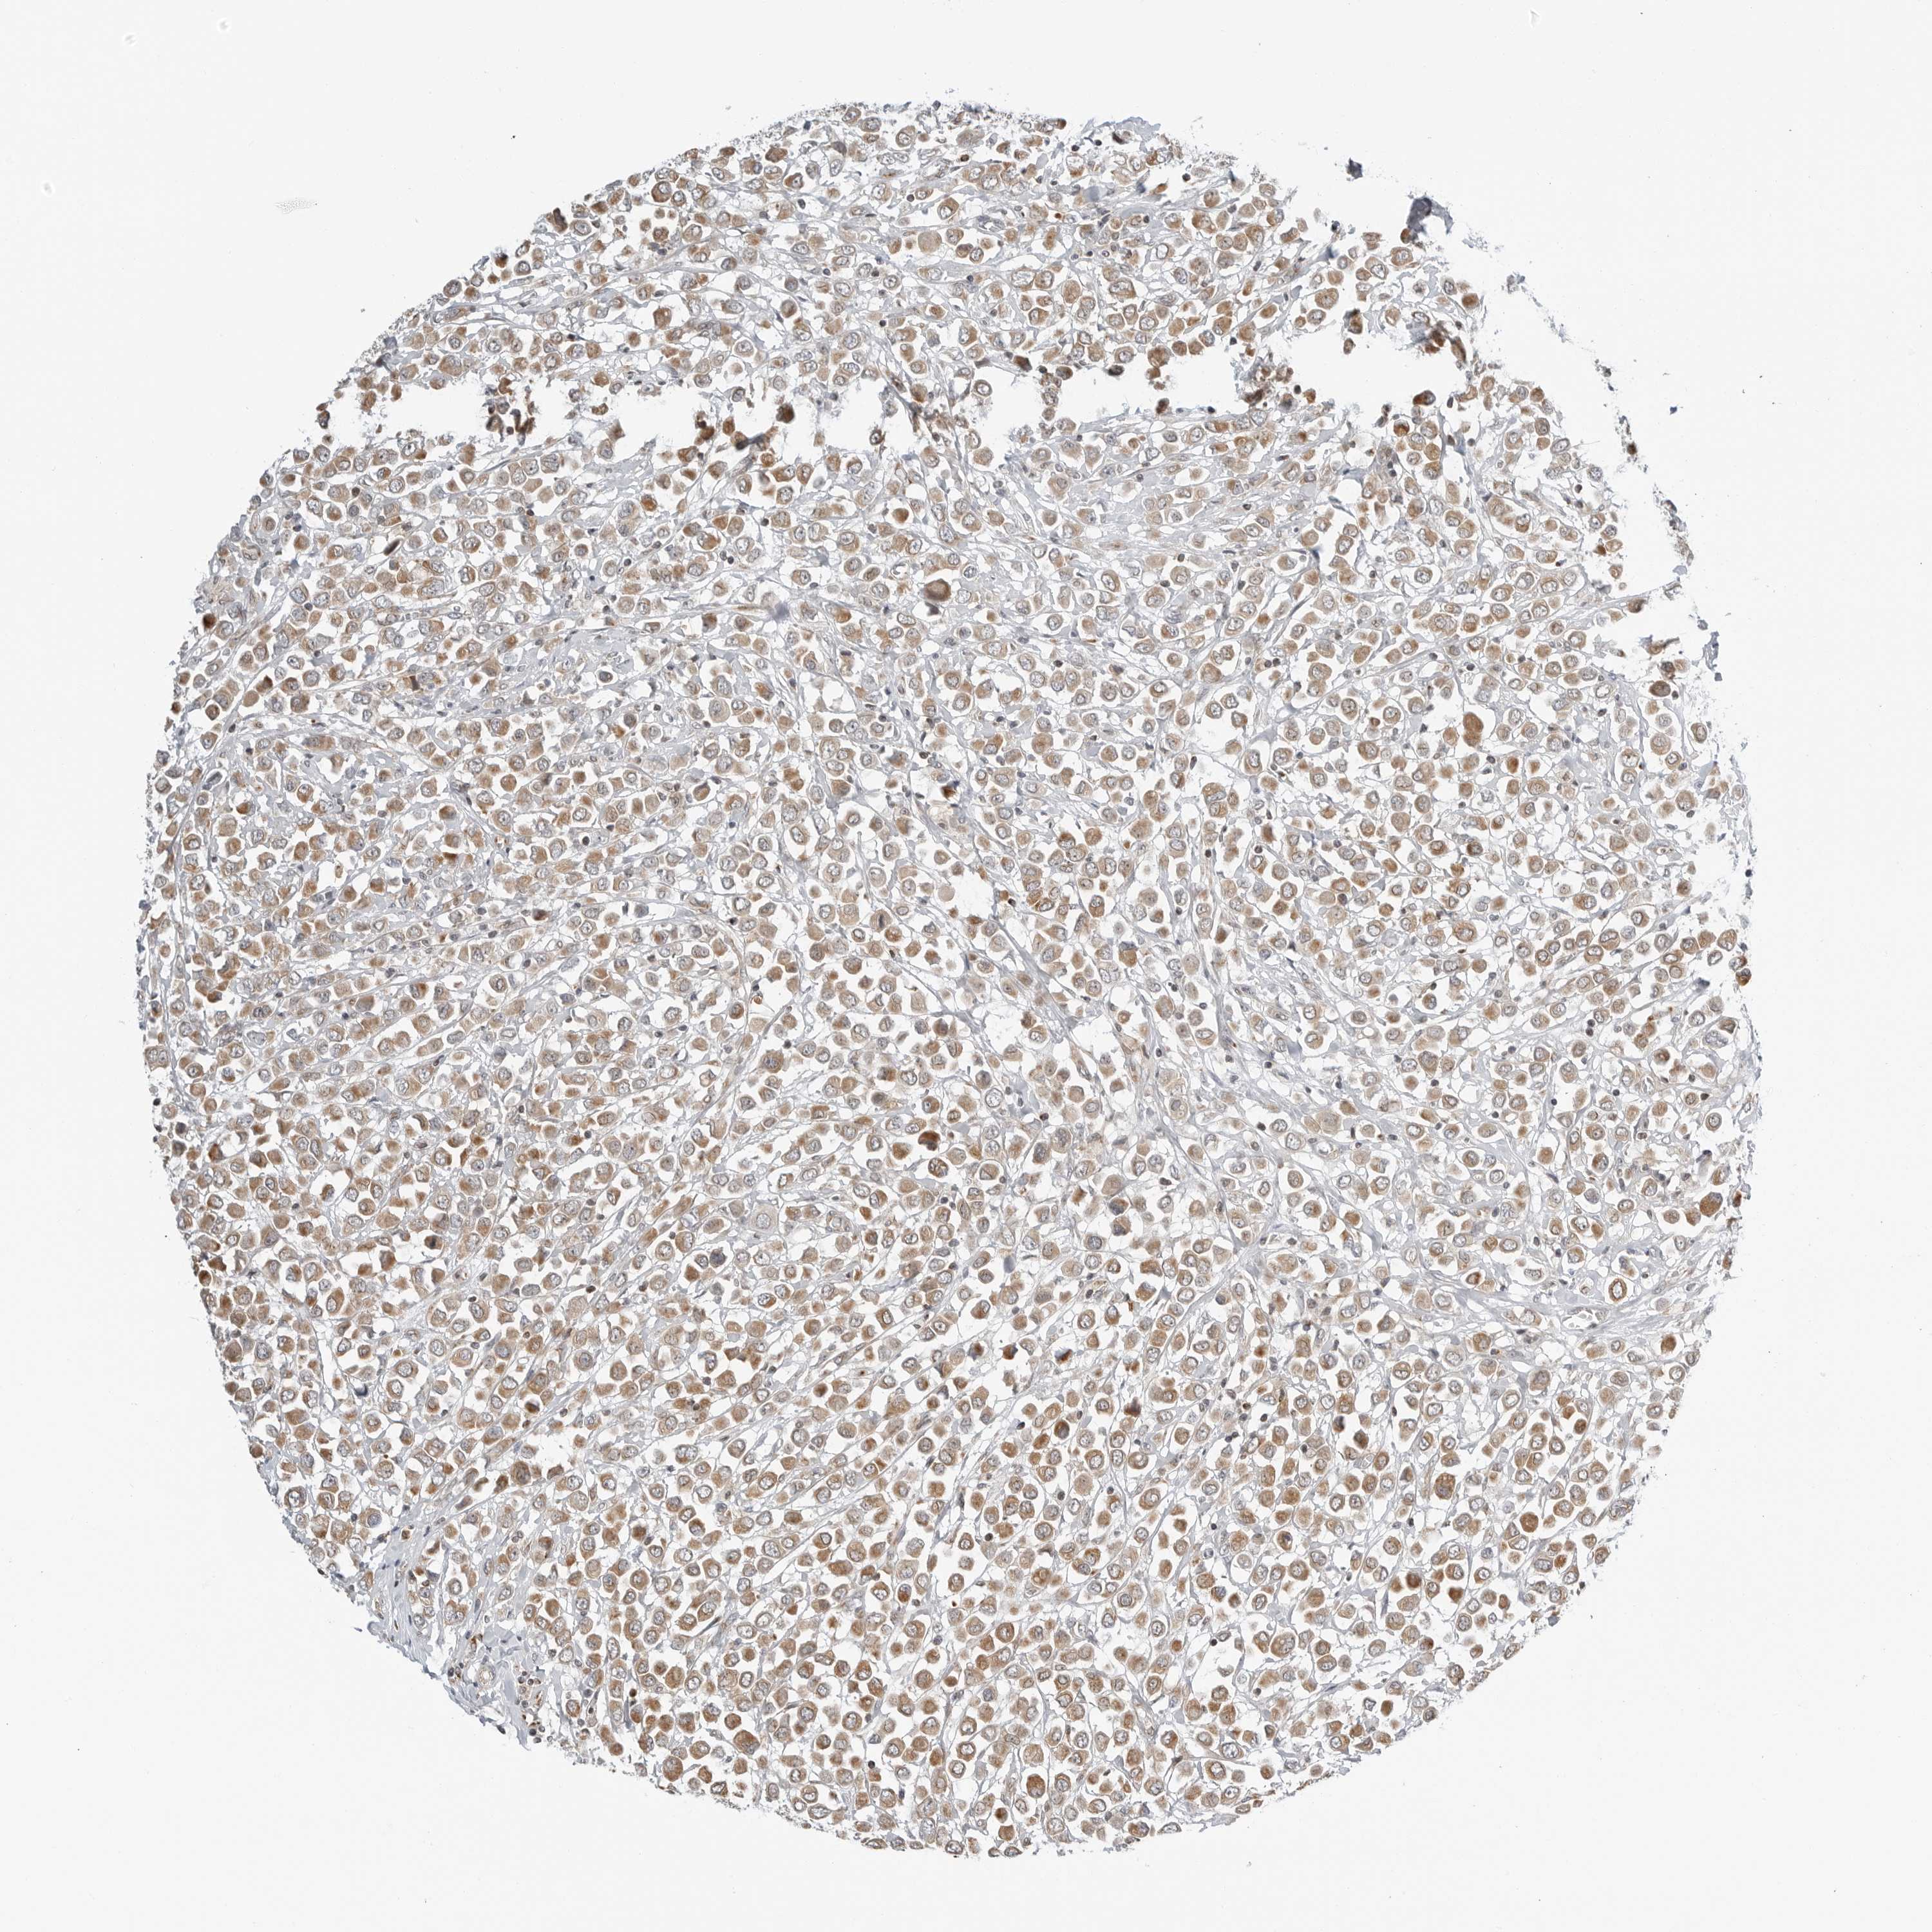

CANCER BREAST CANCER Show tissue menu

BRCA TCGA BRCA VALIDATION PROTEIN EXPRESSION